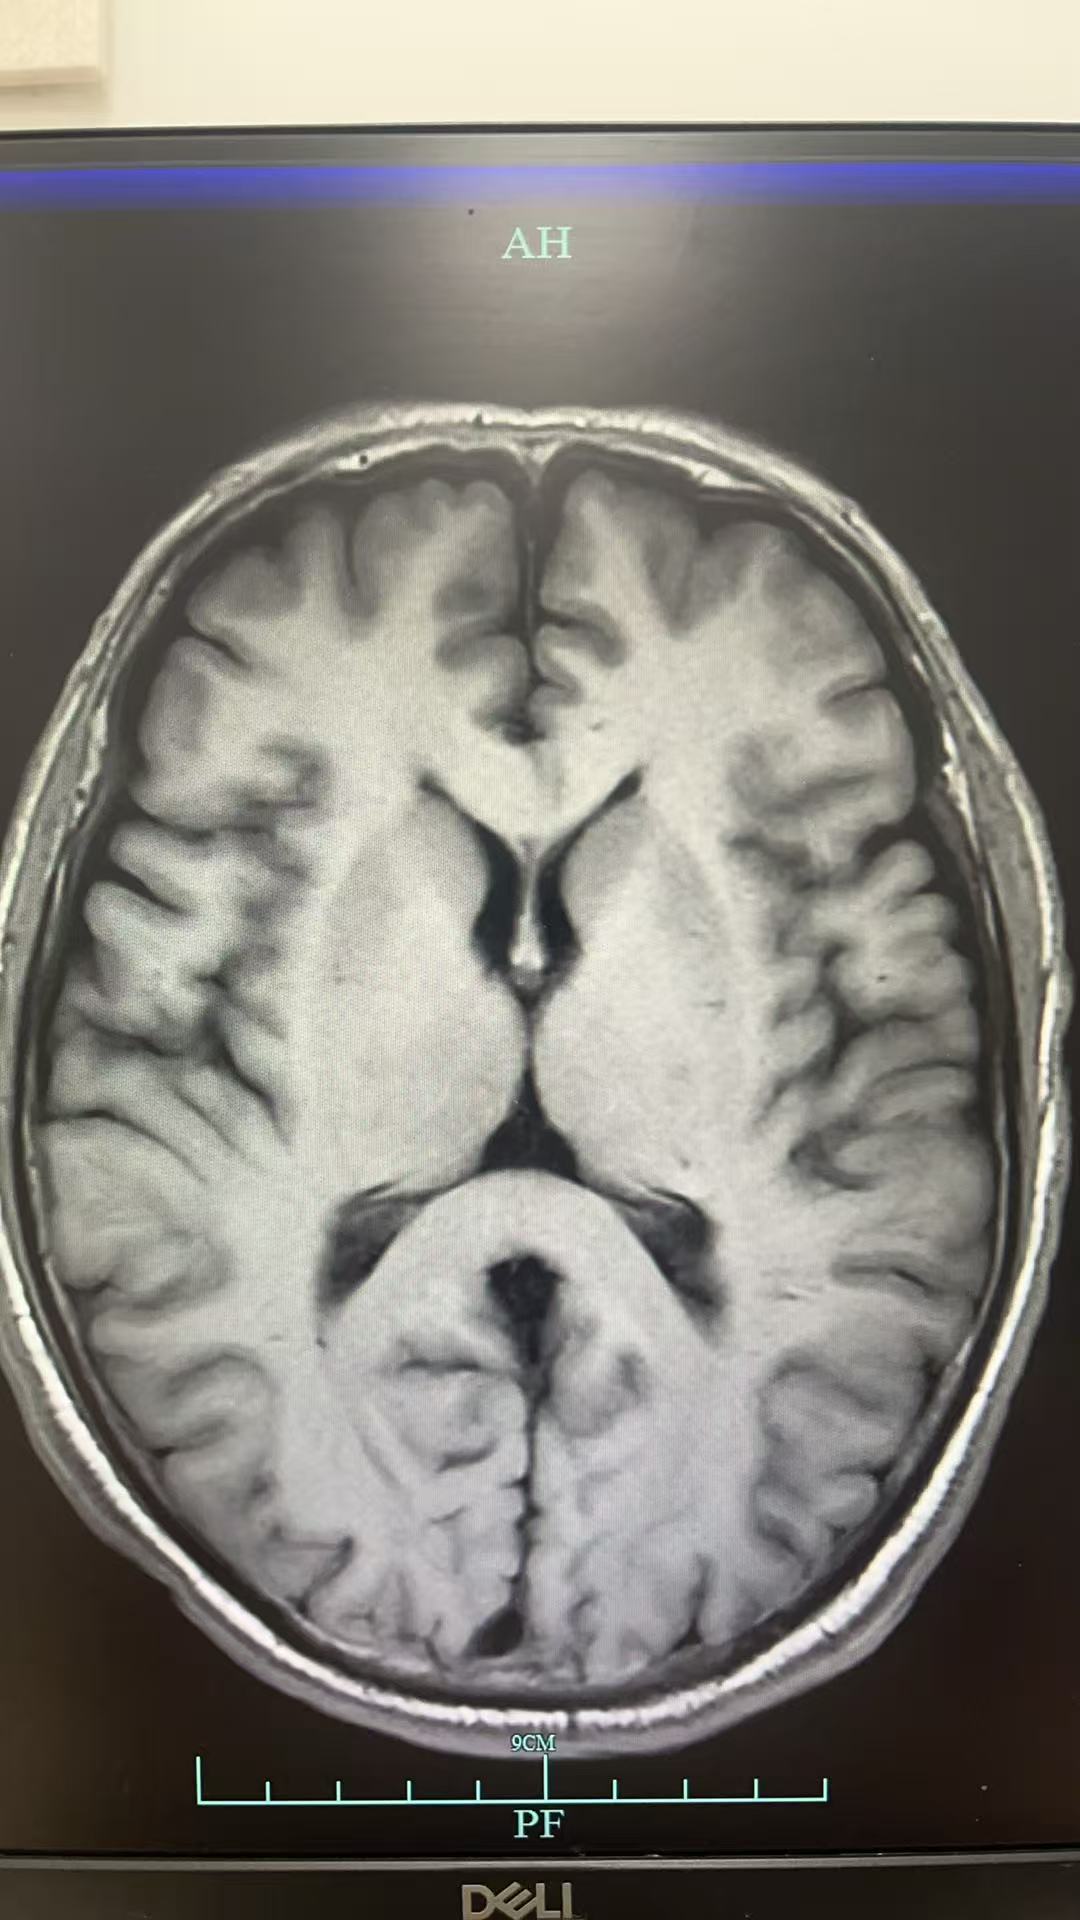

入ICU后因意识情况变差加重,给予气管插管有创机械通气治疗,后完善腰穿,压力正常范围,细胞数目无,并行脑脊液NGS检查,结果全阴;完善脑脊液自免脑抗体检查,结果仍旧为阴性。期间做头颅MRI检查提示:两侧大脑半球硬脑膜增厚强化,请结合临床。右侧额及两侧沈叶可疑部分柔脑膜强化,请结合临床。

神经内科梁主任会诊后认为:患者二月前出现头晕,症状加重,一月前出现精神症状当地头颅MRI示左侧尾状核和枕叶DWI高信号,本院复诊尚可见硬脑膜强化意见,建议床边脑电图,复查腰穿查脑脊液RTQUICE排除克雅氏病可能。查血LGI1抗体,继续甲强龙治疗。随后送的LGI1抗体结果阴性,而脑脊液的RT-QuIC结果为阳性,因此诊断为克雅病。

本案例的突破点在于病史+脑MRI检查结果,对比指南可以看到我们的MRI在尾状核那边也有明显强化的表现。